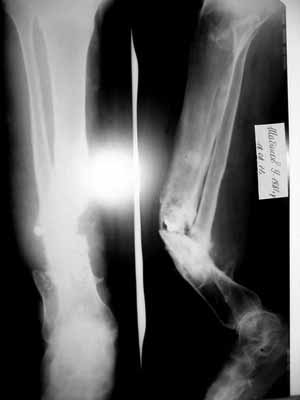

[Ortho] Ложный сустав костей левой голени

Травма в результате ДТП в 2004г., в анамнезе 4 операции

(АВФ, пластина, АВФ, фиксация винтом+ гипсовая лонгета(смысл не ясен)... )Мед.

документацию по данному заболеванию больной не предоставил, всё со слов больного. Помогите

определиться с тактикой лечения. Мы планируем произвести резекцию ложного сустава обеих

костей левой голени, билокальный остеосинтез в аппарате Илизарова с компактотомией в/3 б/б

кости. спс.